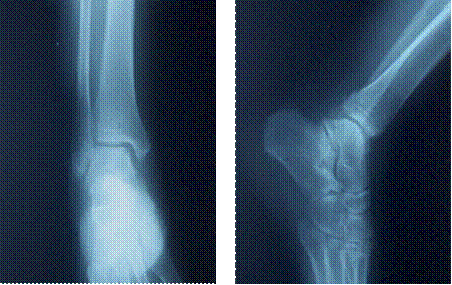

図5 受傷後35日目受傷部レントゲン写真

左 正面像 右 側面像 前後方向の転位改善